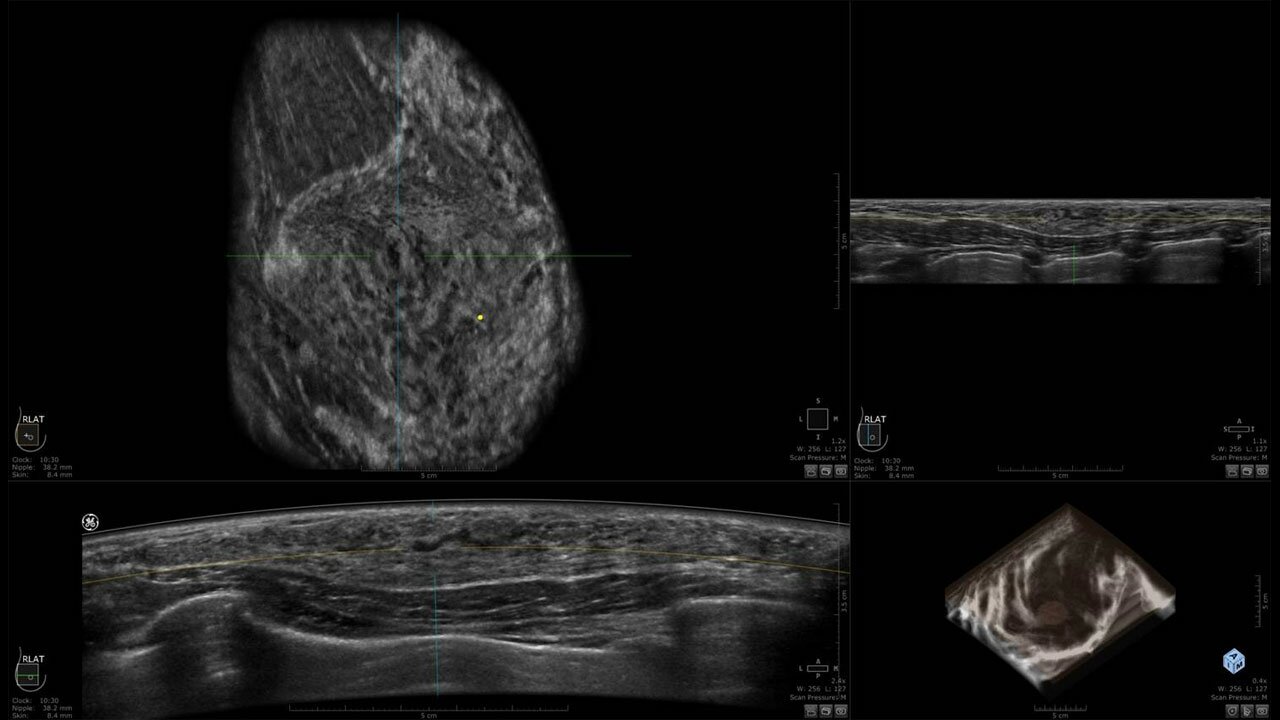

Клинические изображения

• Отображение объемных 3D ультразвуковых изображений, которые состоят из традиционных поперечных и воссозданных коронарных и сагиттальных проекций

• Возможность отображения полного 3D изображения